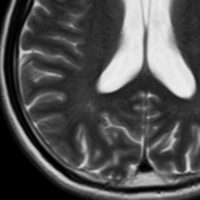

9歳の男の子です。右側頭部が腫れてきたのに気づきました。頭蓋骨のいびつな破壊像があります。

左はMRI T2強調画像です。まるで丸い腫瘍のように見えます。

下のT1強調画像では,ガドリニウム造影剤で強く増強されていて皮下に炎症性腫脹がみられ,活動期の病変であるのがわかります。

この病変は単発(孤発)病変ですが,ややいびつな形をしていて,頭皮の方に盛り上がっていますから,活動性の病変です。手術で完全摘出すると治りますから,骨欠損が広がるようなら手術したほうがいいです。理由は,手術が簡単なこと,病理診断がつくこと,これ以上の病変の広がりを抑えることです。最近は自然の骨に近いような人工骨で補填することができますが,骨形成しなくても自然修復で骨形成されます。とくに,低年齢児では骨形成をしない時もあります,頭蓋骨が自然再生するからです。